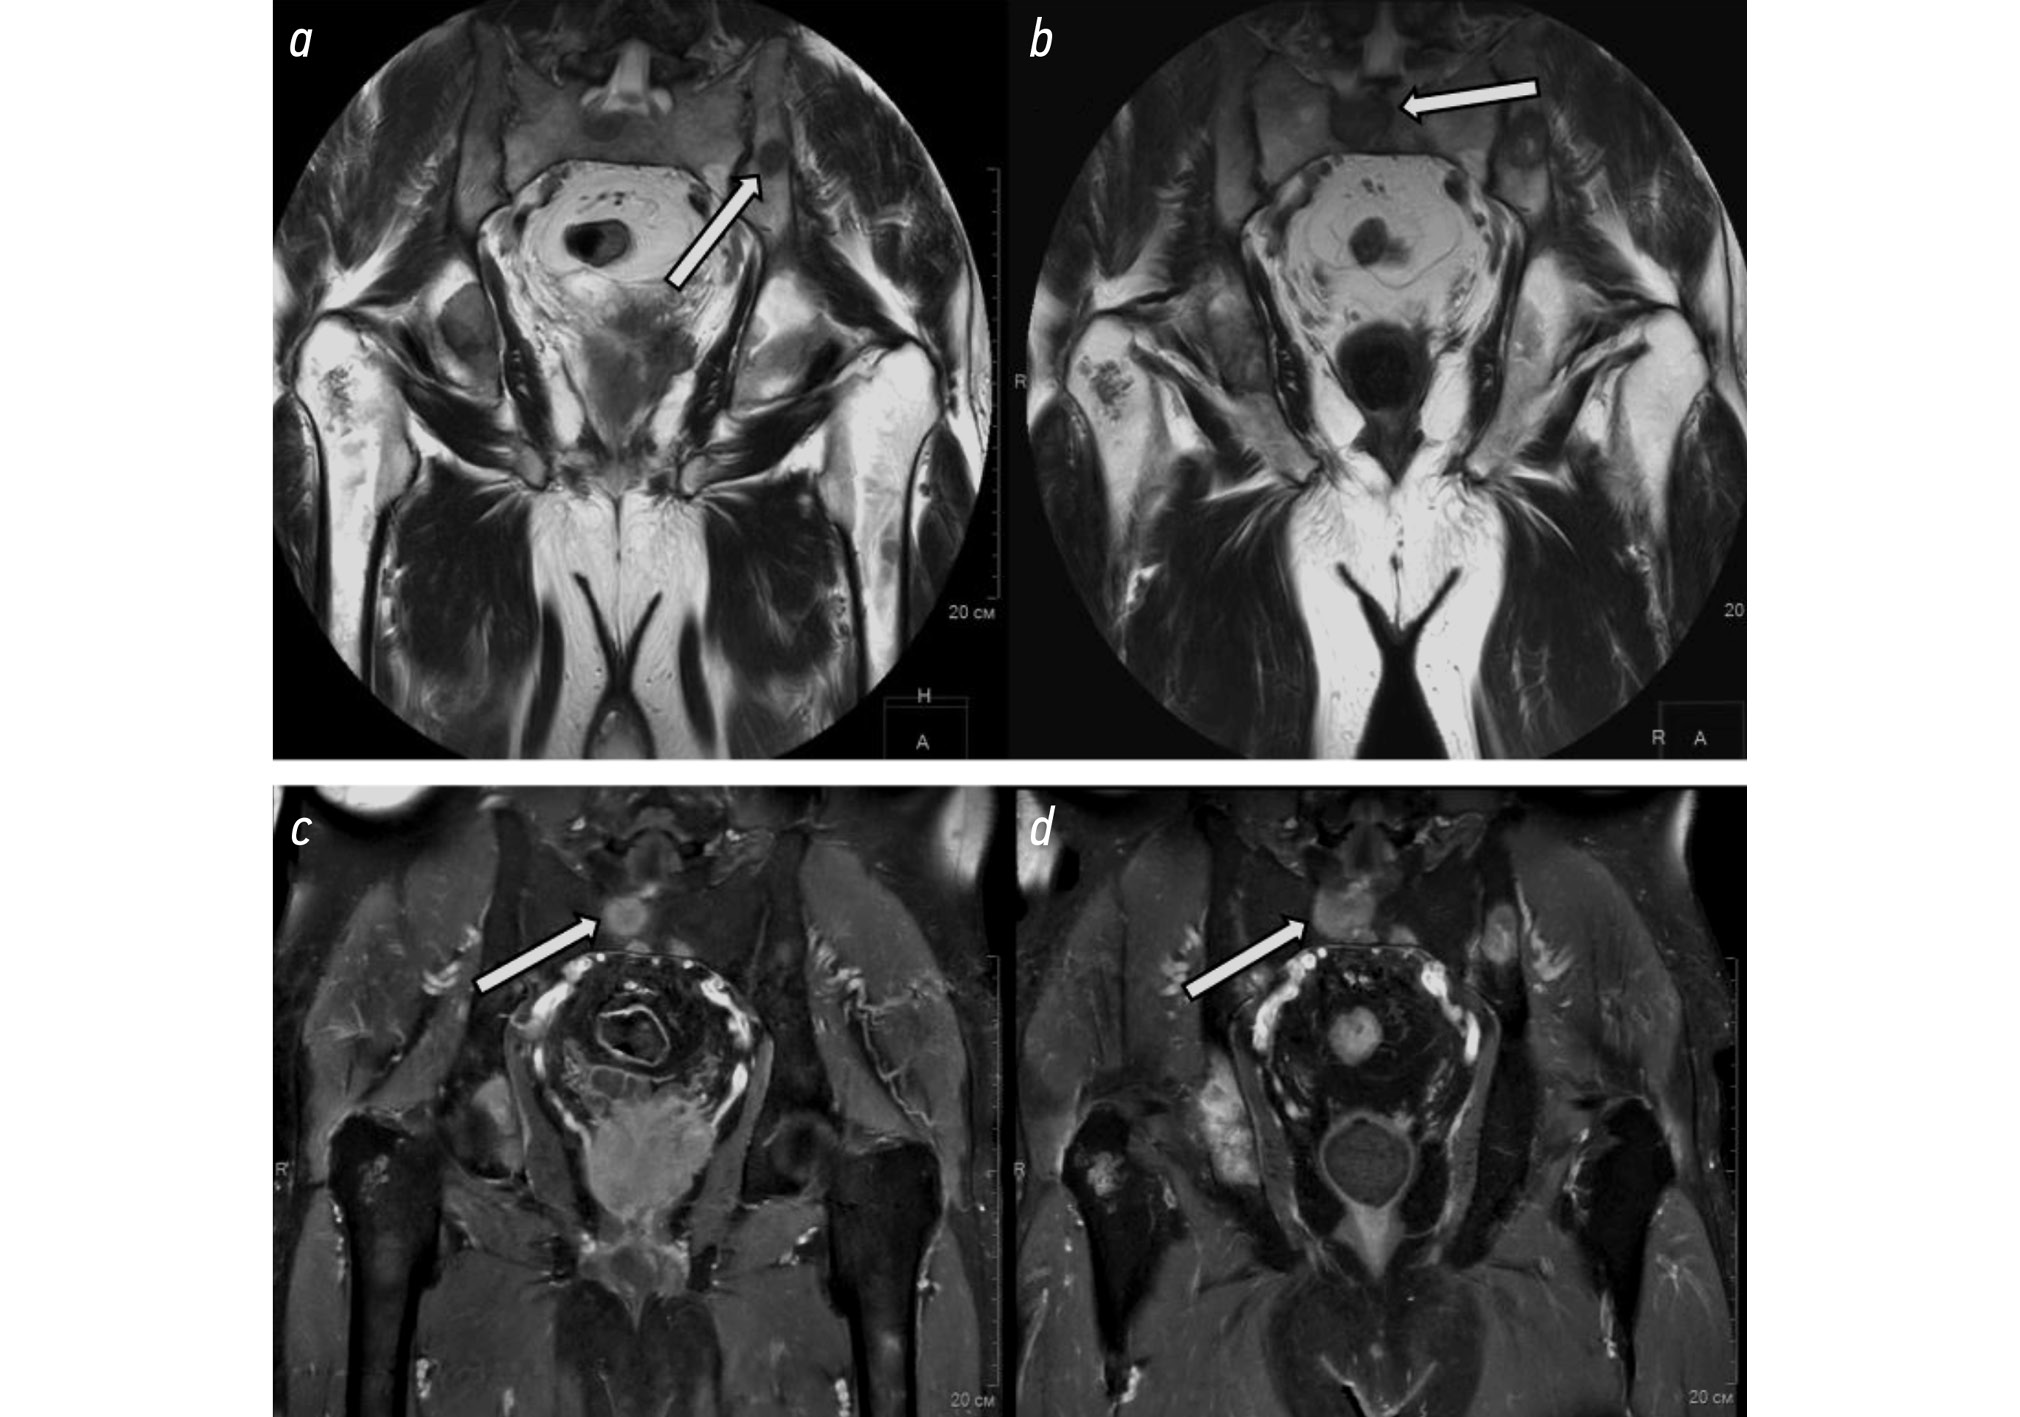

Magnetic resonance imaging is a diagnostic radiological modality that generates images using electromagnetic waves in a constant magnetic field. The advantages of MRI include the lack of ionizing radiation and superior soft tissue imaging. It is one of the most effective techniques for noninvasive bone marrow evaluation (Fig. 2). In addition to anatomical diagnosis, MRI is useful in determining the degree of spinal stenosis and compression, the size and location of lesions, and the extent of vascular supply [23]. The disadvantages include a lengthy scan time and a variety of contraindications, such as the presence of pacemakers and metal implants [26, 27].

Fig. 2. a, b, Pelvic MRI, coronal plane, T2WI; c, d, pelvic MRI, coronal plane, T1WI; case follow-up a, c of February 2023 and b, d July 2023: osteoblastic lesions in pelvic bones, increase in lesion size during follow-up (white arrows).